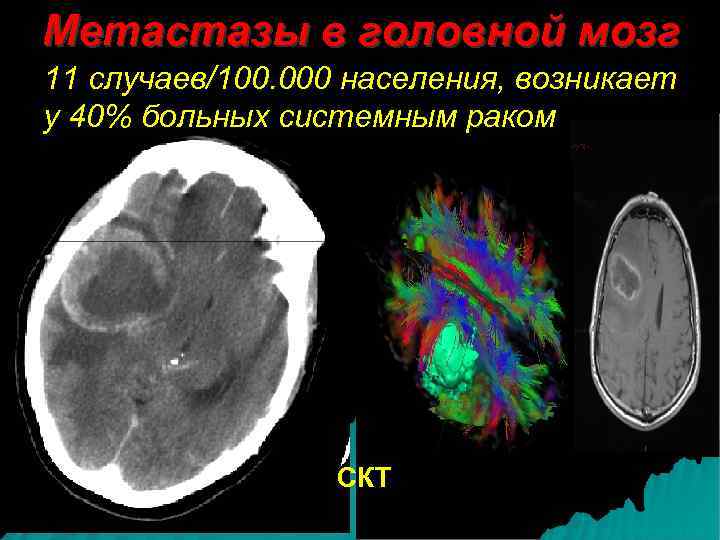

Метастазы в головной мозг 11 случаев/100. 000 населения, возникает у 40% больных системным раком СКТ